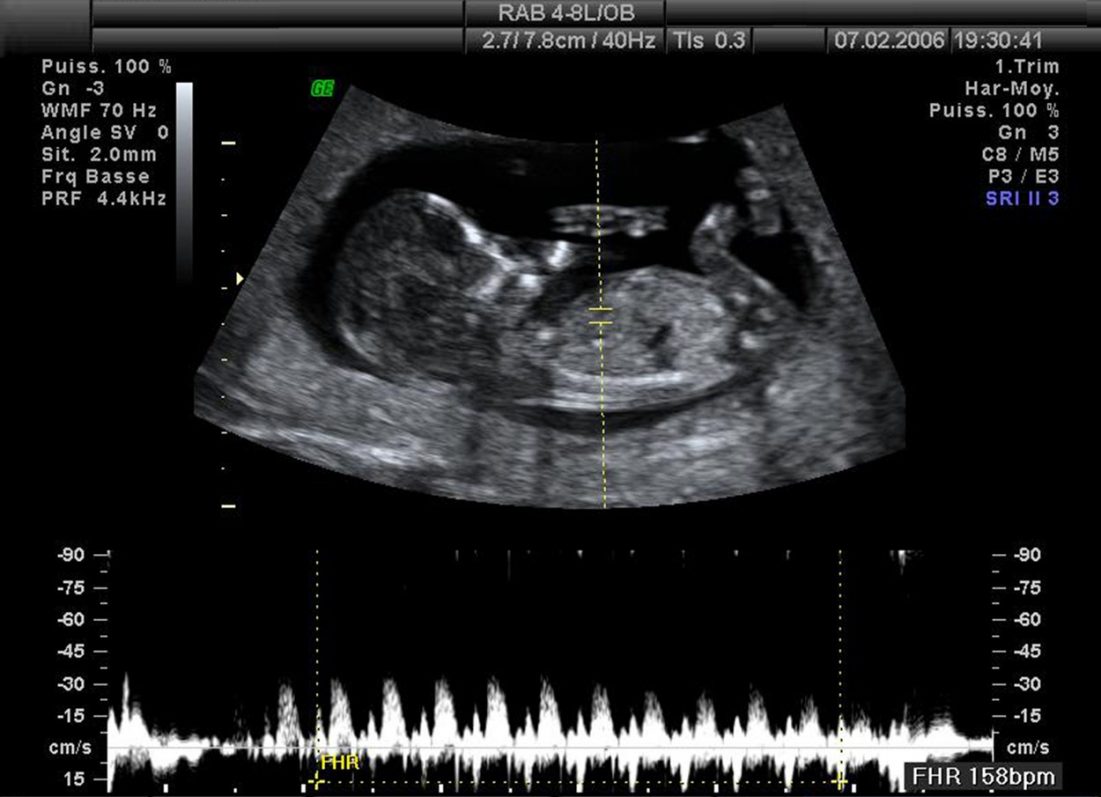

Snímek z 2D ultrazvuku

Při 3D ultrazvuku je série klasických dvourozměrných (2D) obrázků rekonstruována do obrázku 3D a vy tak máte možnost vidět téměř reálný plastický obraz svého dítěte.